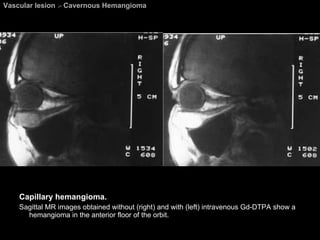

Vascular lesion  >  Cavernous Hemangioma Capillary hemangioma.  Sagittal MR images obtained without (right) and with (left) intravenous Gd-DTPA show a hemangioma in the anterior floor of the orbit.